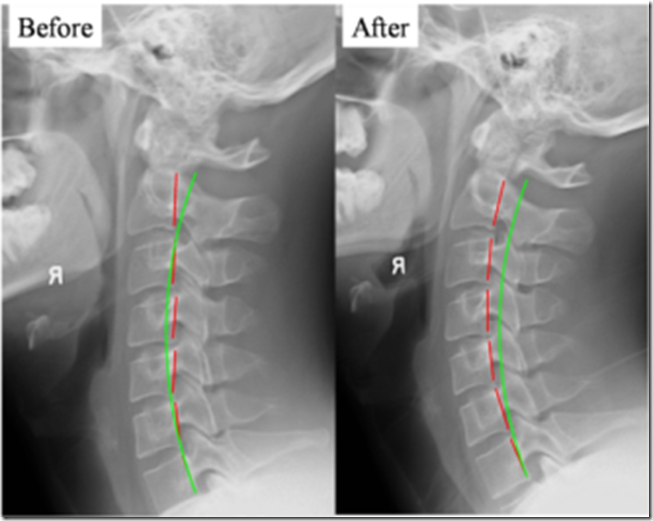

From liachiro.com

I have a reverse cervical curve. Is this a problem? Can you fix it? Chiropractor Auburn Hills What Causes Reverse Curve In Neck cervical kyphosis, or military neck, occurs when your cervical spine is straight or curves toward your front instead of its natural curve. All of us, at one time or another, have probably been told to stand or sit up. Just like when your car’s wheels are out of alignment, this will cause. one main cause of reverse cervical. What Causes Reverse Curve In Neck.